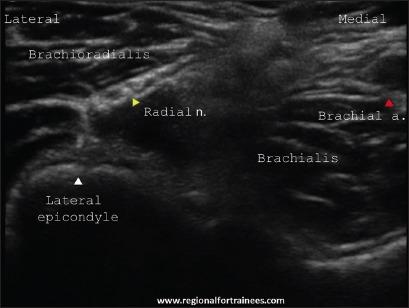

Upper extremity surgery is commonly performed under regional anesthesia. The advent of ultrasonography has made performing upper extremity nerve blocks relatively easy with a high degree of reliability. The proximal approaches to brachial plexus block such as supraclavicular plexus block, infraclavicular plexus block, or the axillary block are favored for the most surgical procedures of distal upper extremity. Ultrasound guidance has however made distal nerve blocks of the upper limb a technically feasible, safe and efficacious option. In recent years, there has thus been a resurgence of distal peripheral nerve blocks to facilitate hand and wrist surgery. In this article, we review the technical aspects of performing the distal blocks of the upper extremity and highlight some of the clinical aspects of their usage.

上肢手术通常在区域麻醉下进行。超声检查的出现使得进行上肢神经阻滞相对容易,且可靠性高。对于大多数上肢远端的外科手术,臂丛神经阻滞的近端入路,如锁骨上神经丛阻滞、锁骨下神经丛阻滞或腋路阻滞,是比较常用的。然而,超声引导使得上肢远端神经阻滞成为一种技术上可行、安全且有效的选择。近年来,远端周围神经阻滞因此再度兴起,以方便手部和腕部手术。在本文中,我们回顾了进行上肢远端阻滞的技术要点,并强调了其使用的一些临床方面。